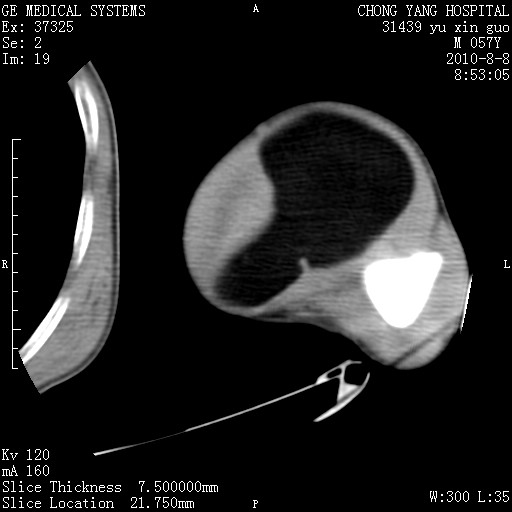

标题: CT28267:M57Y 上臂包块8年余。 [打印本页]

标题: CT28267:M57Y 上臂包块8年余。

软组织内脂肪瘤

包膜光滑、完整的脂肪密度肿块,支持脂肪瘤。